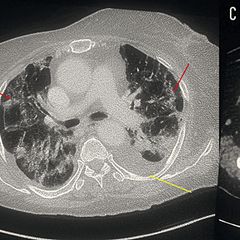

COVID-19 Presenting as Encephalitis and Myopericarditis: A Report of a Rare Case...

COVID-19 Presenting as Encephalitis and Myopericarditis: A Report of a Rare Case  Cureus